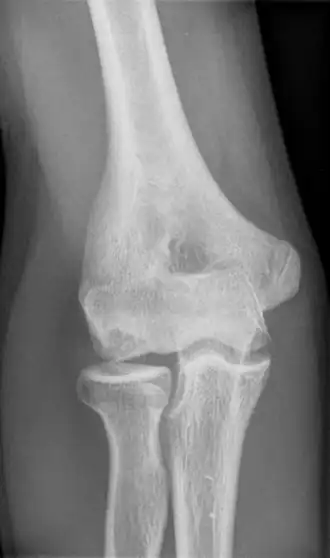

Description de l'image Panner 16J.png.

La maladie de Panner (ou ostéochondrose du capitulum )[1] est une nécrose avasculaire localisée au niveau du capitulum de l'humérus menant à une perte d'os sous-chondral fissurant les surfaces articulaires radio-humérale.